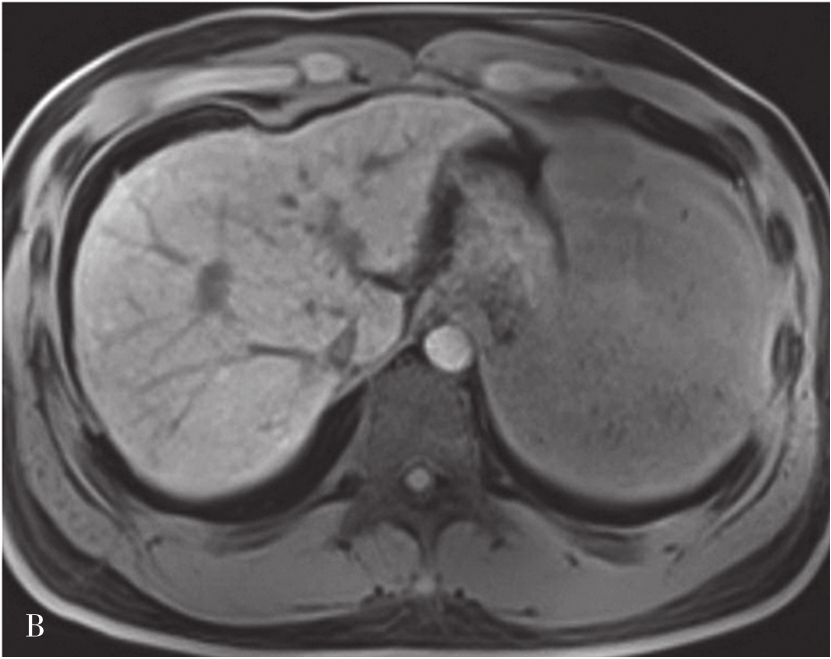

MRI图像,正常肝脏蛋白质含量丰富,自由水含量较少,肝组织的T 1 、T 2 弛豫时间短,T 1 WI呈中等强度的灰阶,与脊髓及胰腺相仿,肝脏信号相对高于脾脏及肌肉(图5-21-40A);T 2 WI则低于脾脏(图5-21-40B)。肝内血管和胆管在T 1 WI通常表现为低信号,T 2 WI胆管呈高信号。第二肝门处3根静脉在肝实质衬托下呈“鸡爪状”向腔静脉聚集。正常肝总管及左右肝管一般不被显示,在扩张情况下表现为门脉前方与之伴行的管道结构,信号略高于门脉。MRI上观察肝脏是否正常,一般要从肝脏形态、大小、信号是否异常,肝的分叶分段是否俱全、轮廓是否光整、表现是否光滑、肝裂是否增宽、质地是否细腻、信号是否均匀、血管纹理是否走行自然等多方面去评价。

图5-21-40 正常T 1 WI及T 2 WI图像

A.正常T 1 WI图像;B.正常T 2 WI图像